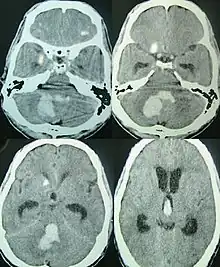

Tomografia axial mostrando hemorragia na fossa posterior[6]

Sangramentos intracerebrais são a segunda causa mais comum de AVC, representando 10% das internações hospitalares pela doença.[7] A pressão arterial elevada aumenta os riscos de hemorragia intracerebral espontânea de duas a seis vezes.[6] Mais comum em adultos do que em crianças, sangramentos intraparenquimatosos geralmente são devidos a traumatismo craniano penetrante, mas também podem ser decorrentes de fraturas de crânio deprimido. O trauma de aceleração-desaceleração,[8][9][10] ruptura de um aneurisma ou malformação arteriovenosa (MAV) e sangramento dentro de um tumor são causas adicionais. A angiopatia amiloide é uma causa não comum de hemorragia intracerebral em pacientes com idade superior a 55 anos. Uma proporção muito pequena é devida a trombose do seio venoso cerebral.

A hemorragia intraparenquimatosa pode ser reconhecida na tomografia computadorizada porque o sangue aparece mais brilhante do que outro tecido e é separado da mesa interna do crânio por tecido cerebral. O tecido que envolve um sangramento é muitas vezes menos denso do que o resto do cérebro por causa do edema e, portanto, aparece mais escuro na tomografia computadorizada.[14]